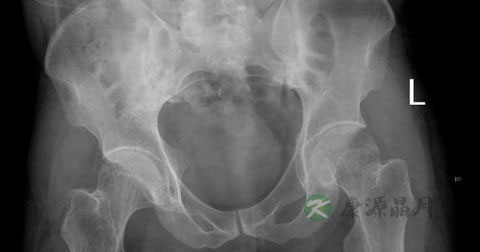

强直性脊柱炎是以骶髂关节和脊柱附着点炎症为主要症状的疾病。强直性脊柱炎属风湿病范畴,是血清阴性脊柱关节病的一种。该病病因尚不明确,是以脊柱为主要病变部位的慢性病,累及骶髂关节,引起脊柱强直和纤维化,造成不同程度眼、肺、肌肉、骨骼病变,属自身免疫性疾病。

3、通常最早发病的位置是在骶髂关节,疼痛可放射到臀部及大腿后侧,有时可至大腿外侧或前侧,通常不会到达膝盖以下,随着疾病的进展,发炎渐渐向腰椎、胸椎进行,最后可影响颈椎,脊椎的活动范围变差,初期为后弯侧弯受限,晚期时前弯亦受限。

5、有部分病人会有周边关节炎,其中以髋关节最多,其它常见的是肩关节、膝关节、踝关节等,大约有四分之一的病人有髋关节炎,严重时会造成关节活动受限、下蹲困难、跛行、两脚不等长。